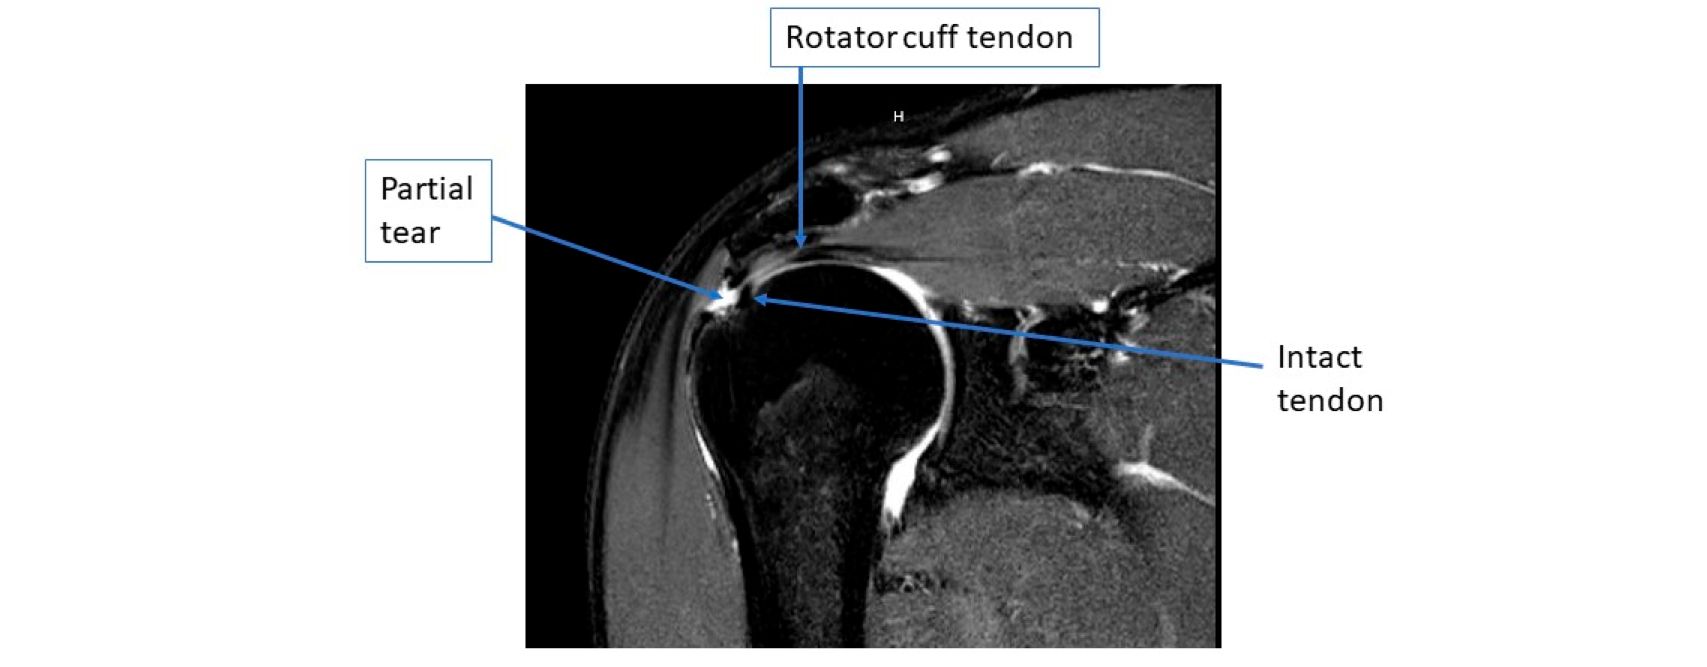

MRI image of a partial thickness rotator cuff tear.